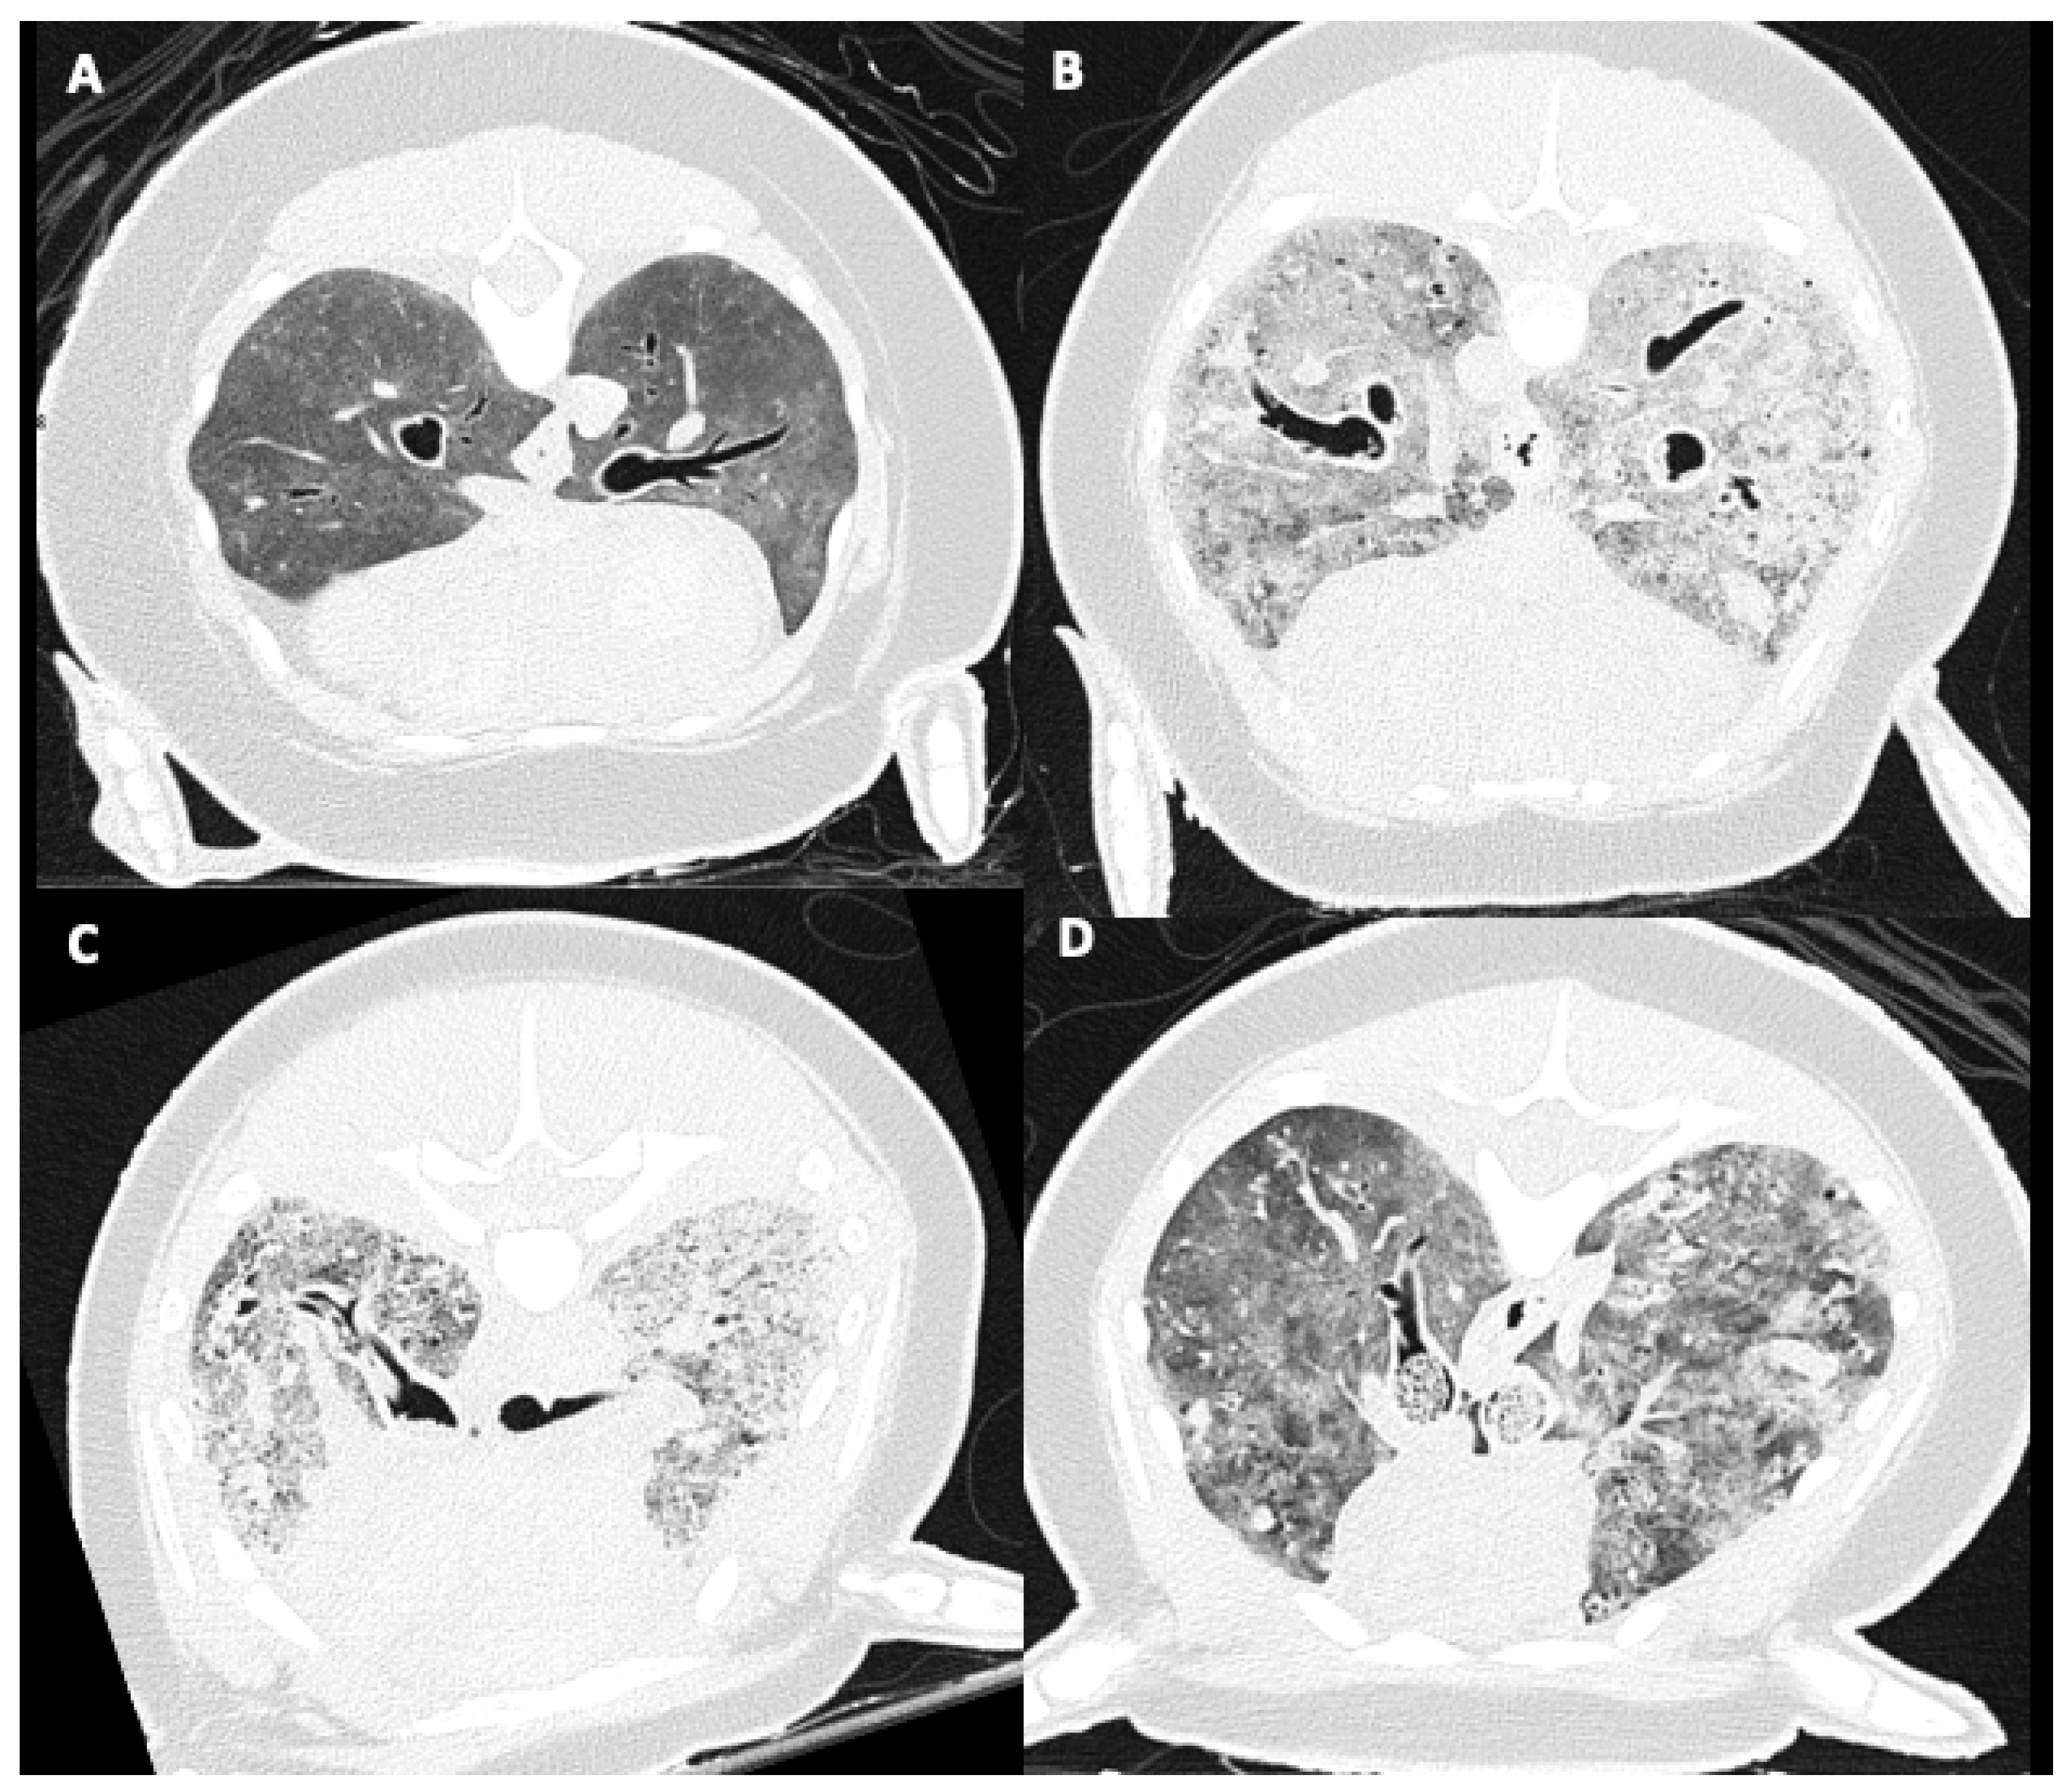

2.5. Pulmonary Parenchymal Attenuation Changes

3.4. Pulmonary Parenchymal Attenuation Changes